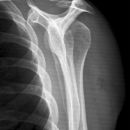

Schulter a.p. (Schultergelenk nach Grashey)

Beurteilungskriterien

- Außenrotation ->Tuberculum majus lateral randbildend, Innenrotation ->Tuberculum minus medial randbildend

- Gelenkspaltweite 4-6 mm

- Weite des subacromialen Raumes exakt nur in der 10 – 15° nach kaudal angulierten Aufnahme bestimmbar ("Morrison, Outlet View")! Normalerweise 1 - 1,5 cm, < 6 mm -> wohl pathologisch, Impingment röntgenlog. wahrscheinlich, Cave. rein klinische Diagnose!

- Normvarianten: Os glenoidale (akzessorischer Ossikel kaudal des Glenoids), persistierende Akromion- oder Korakoidapophyse, entwicklungsbedingte Pfannenranddefekte